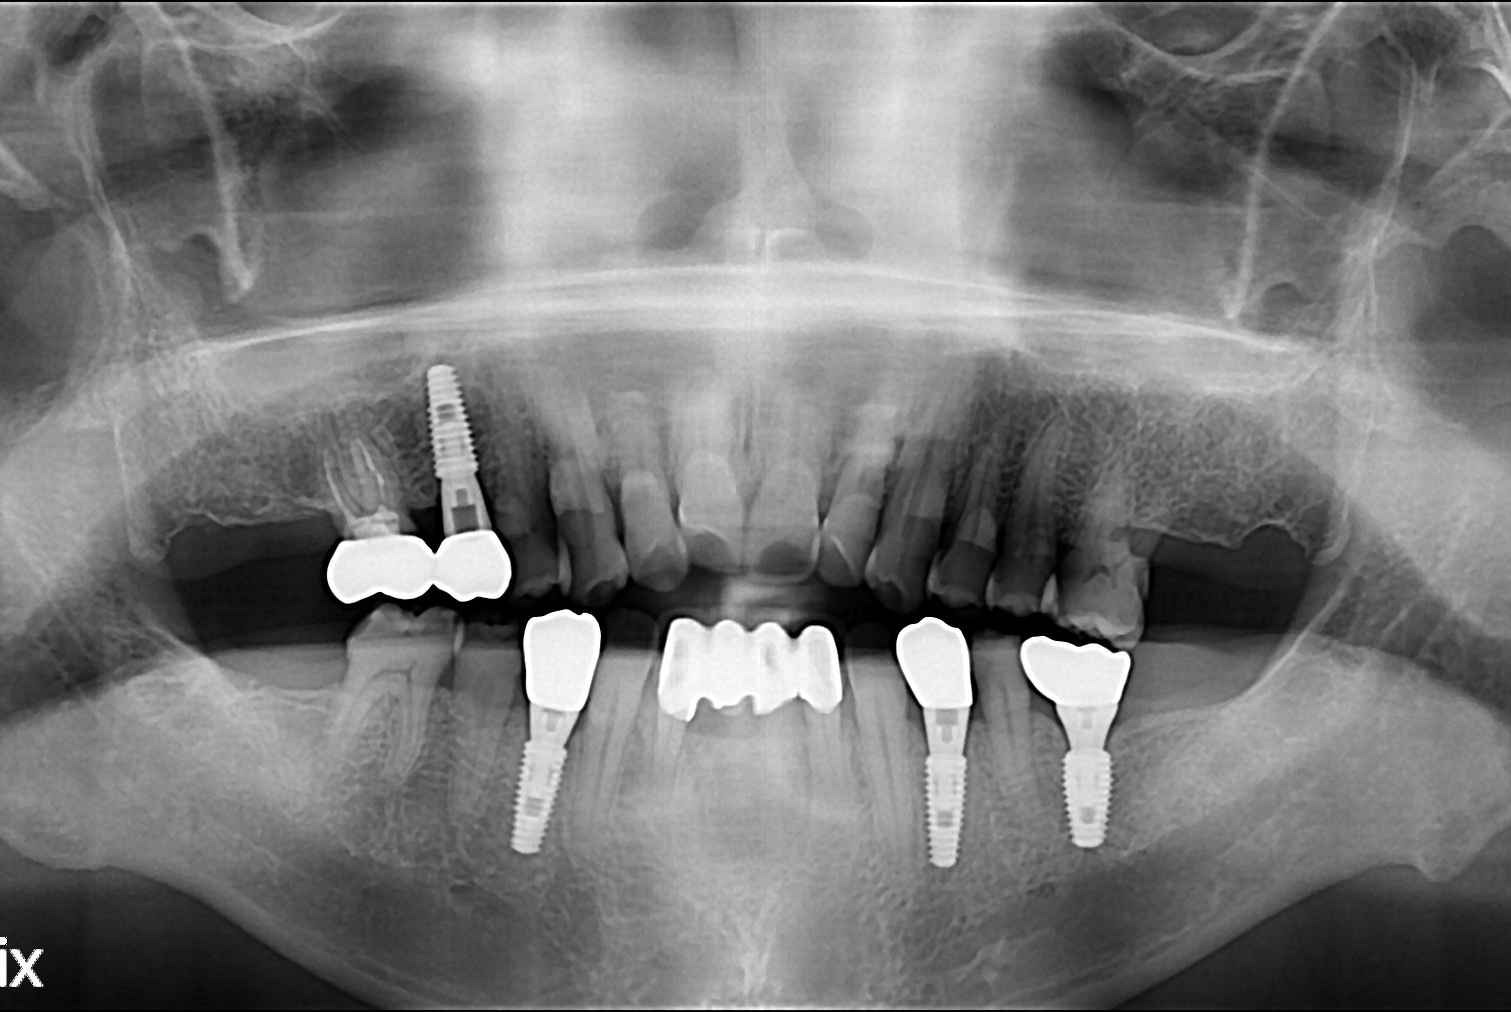

치료전 : 2017-10-02

치료후 : 2017-11-30

세종치과는 많은 환자와 다양한 케이스를 바탕으로 항상 편안한 임플란트 수술을 제공하고자 노력하고,

오래동안 튼튼히 쓸 수 있는 임플란트 수술을 가장 큰 목표로 삼고 있습니다